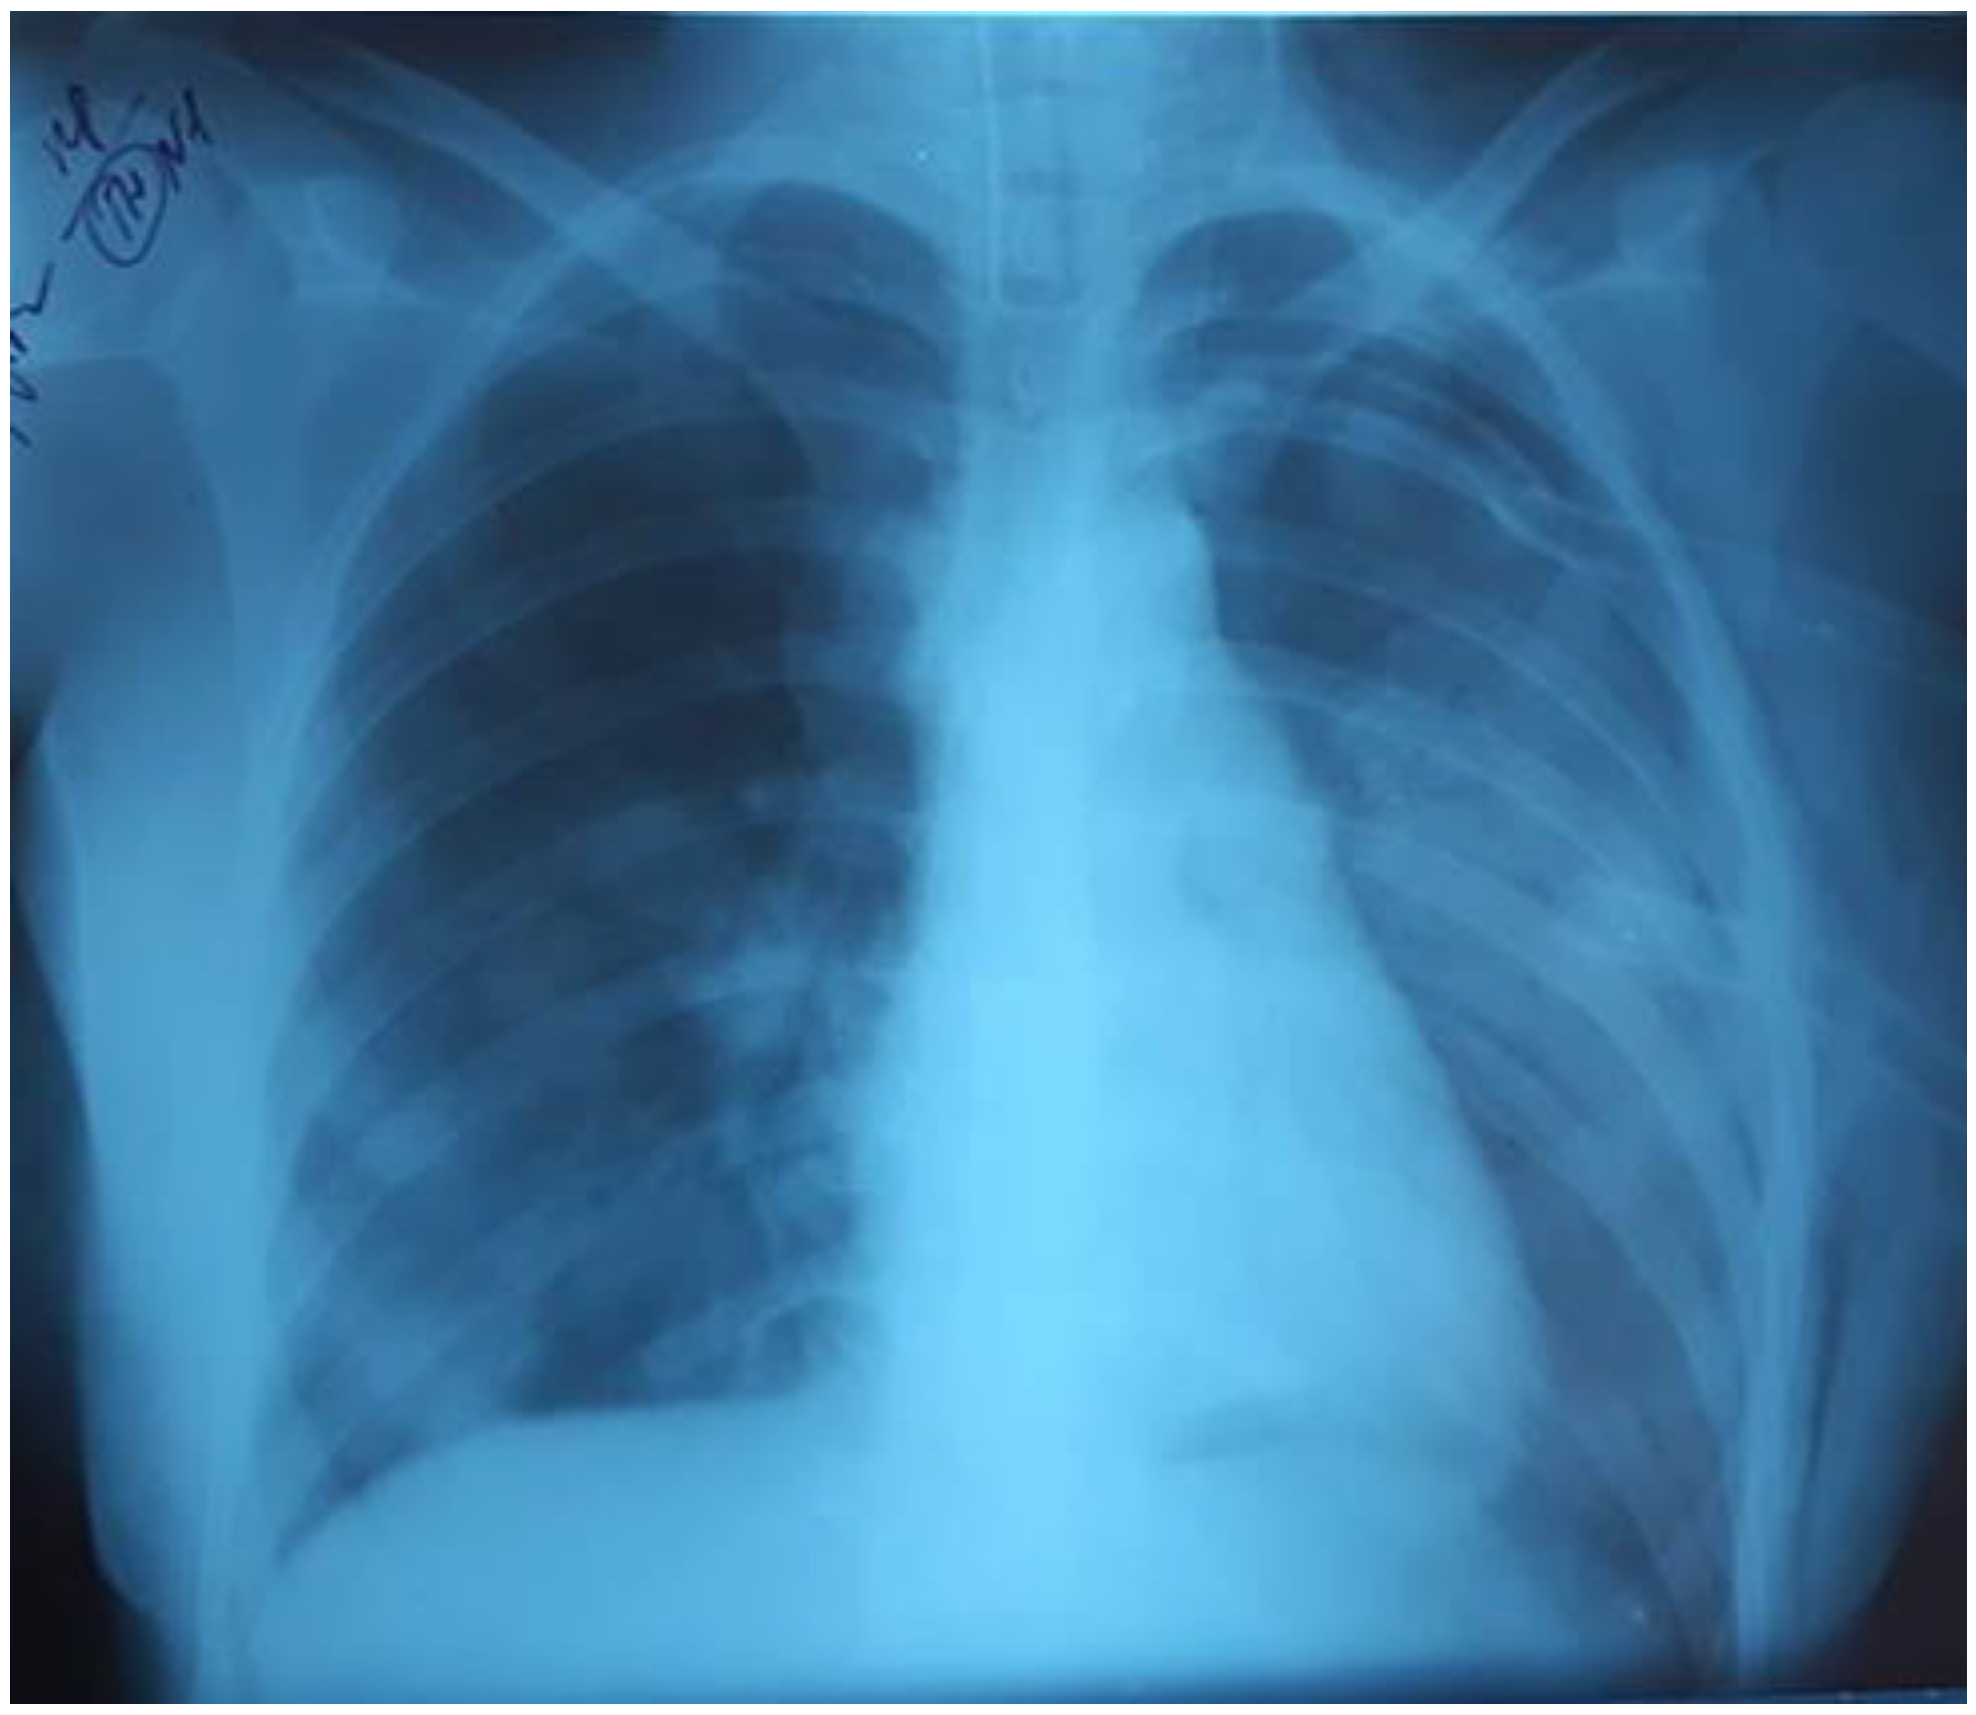

On the third day of mechanical ventilation, the girl had a complication—left-sided pneumothorax. The urgent drainage of the pleural cavity (Figure 4) was performed, as well as reduction of mechanical ventilation parameters: P/SIMV, FiO2 80%, PIP 12 cmH2O, PEEP 8 cmH2O, I/E 1-1.5, TV 300 mL/kg.

Figure 4.

Left-sided pneumothorax.

Over the next 24 hours, there was a progressive decrease in oxygenation: PaO2/FiO281, PaO2 80 mmHg, PaCO2 61 mmHg. The chest radiograph showed that the left lung was partly collapsed; there was an active air discharge through the drainage. The drainage of the left pleural cavity and the second drainage were performed (Figure 5).

Figure 5.

The left lung was partly collapsed.